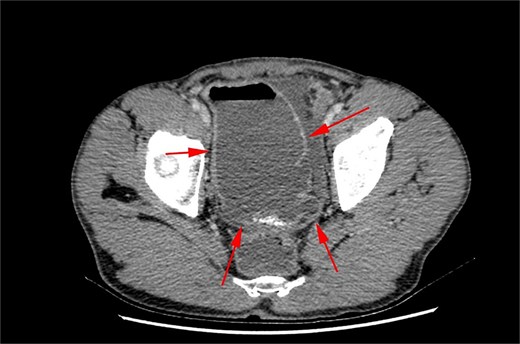

After intravascular fluid resuscitation, exploratory laparotomy was performed with findings below (Fig. 3):

300 cc seropurulent pelvic collection within the right lower quadrant

A grossly dilated, inflamed appendix with 0.5 cm perforation midway along its length

20 × 12 cm diverticulum to ileum, approximately 60 cm from the ileocecal valve

Fecalith in situ

Enlarged mesenteric lymph nodes

An intraoperative diagnosis of acute ruptured appendicitis with and giant MD was made. An appendectomy was performed, followed by a segmental ileal resection incorporating the diverticulum (Fig. 4). A primary, end-to-end, hand-sewn, single-layer ileo-ileal anastomosis was constructed using 2–0 silk.